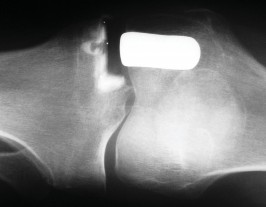

الأشعة السينية العادية (Plain Radiographs):

- المنظر الأمامي الخلفي (AP): يُظهر الركبة من الأمام.

- المنظر الجانبي (Lateral): يُظهر الركبة من الجانب.

- المنظر الخلفي الأمامي المثني (PA Flexed): يسمح بتقييم أفضل للجزء الخلفي من الركبة وقد يكشف عن تغيرات أكبر في الحجرة الخلفية الوحشية.

- منظر شروق الشمس (Sunrise/Patellofemoral): لتقييم المفصل الرضفي الفخذي.

- الأشعة السينية الطويلة للطرف السفلي بالكامل (Full-length standing radiographs): من الورك إلى الكاحل، وهي مفيدة جدًا، خاصة إذا تم استخدام تقنيات الملاحة الحاسوبية. تُظهر هذه الأشعة المحاذاة الكلية للطرف السفلي.